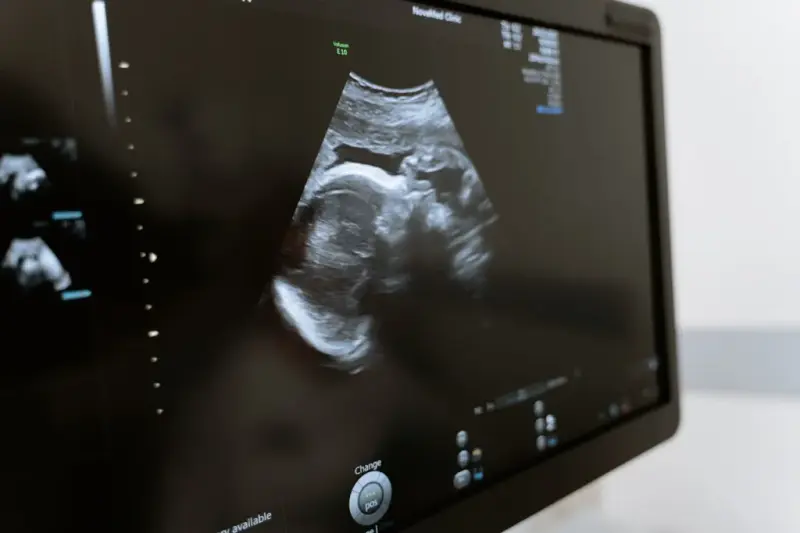

Rola USG w ginekologii i położnictwie

Ultrasonografia w ginekologii i położnictwie to narzędzie nie do przecenienia. Pozwala na monitorowanie rozwoju płodu, ocenę stanu narządów rodnych oraz wykrywanie ewentualnych nieprawidłowości.

W trakcie ciąży USG jest wykonywane kilkukrotnie, aby sprawdzić, czy rozwój dziecka przebiega prawidłowo. Dzięki temu przyszli rodzice mogą zobaczyć swoje dziecko jeszcze przed narodzinami, a lekarze mają możliwość wczesnego wykrycia wad rozwojowych.